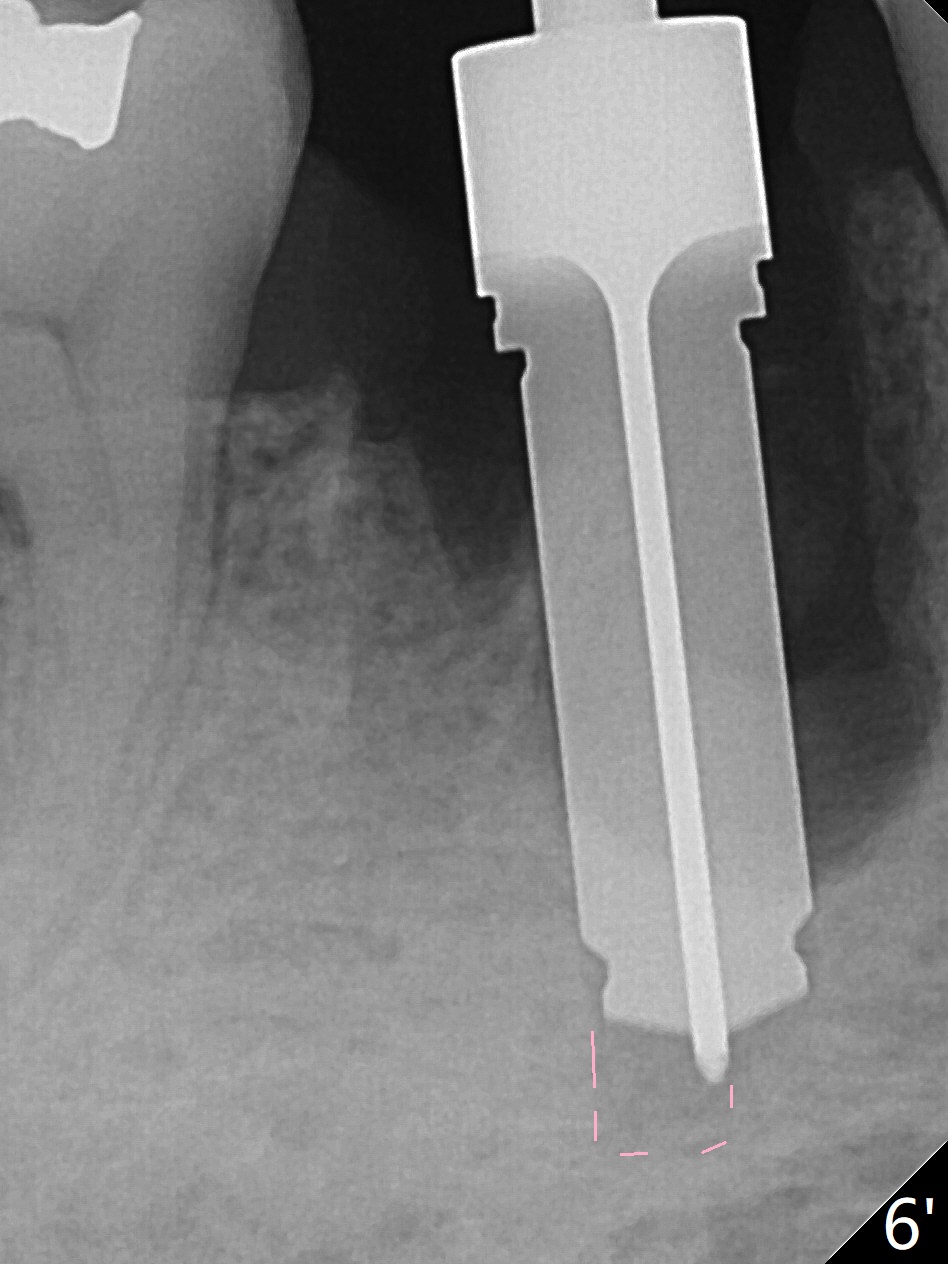

Preop oral Amoxicillin seems to be associated with reduction in the buccal and lingual (Fig.3 arrow) fistulae at #30, but there is mesiobuccal swelling (Fig.1 *) with 7 mm pocket (Fig.2). Osteotomy is initiated in the middle of the septum (Fig.3-5 S). As the osteotomy increases, it shifts mesially (Fig.6 arrow). Guided surgery is able to reduce shifting. A 5x13 mm implant is not seated completely (Fig.7) apparently due to osteotomy shifting. After removal of the bone from the osteotomy distally, the implant remains unseated with lower torque value (Fig.8). Following reuse of the 4.3 mm drill deeper by 1-2 mm, the implant is seated to a satisfactory depth (Fig.9 with increase in torque to 50 Ncm) with placement of Vera Graft (*) and a 7.5x4(3) mm abutment. After a second round of allograft placement (Fig.10 *), the implant is found to be 4 mm from the IAC. At the later stage of osteotomy, the coronal end of the septum is destroyed with loss of osteotomy depth landmark. It is apparent that the soft tissue landmark may be more reliable. The implant threads appear to be covered by the bone graft 3.5 months postop (Fig.11). The abutment is changed to 6.5x5(3) mm one before impression with minor margin prep. The bone density seems to increase 5 months postop, i.e., immediately post cementation (Fig.12) and 10 months postop (5 months post cementation (after retightening abutment), Fig.13 (*)). Periimplantitis develops mesiobuccally, consistent with bone loss 1 year 7 months post cementation (Fig.14 *); the implant seems to have been buccally placed. Bone graft is necessary with PRF or GEM21S if the vein is small and 6-month membrane with a hole around a 7.5x4(4) cemented abutment for easy wound closure. Take 5x5 CM CBCT to determine which wall has defect, buccal or lingual. Check mesial contact. If so, remove the crown, reseat the abutment (possible incomplete seating) and re-impress after bone graft.